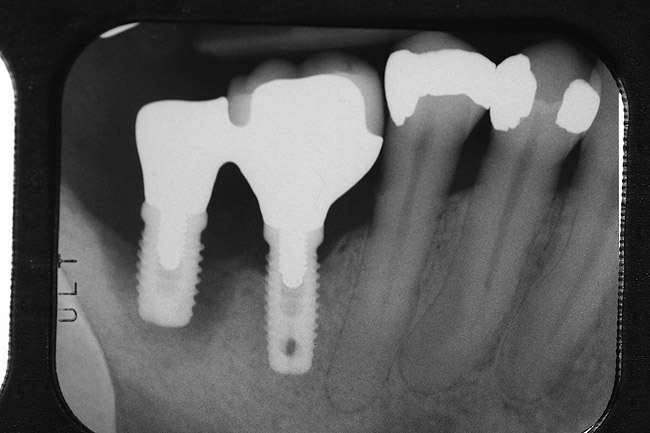

Inflammation limited to soft tissues around a dental implant may result from dental plaque colonization and is termed peri-implant mucositis. This is a reversible inflammatory condition limited to the soft tissues around the implant (without any bone loss), analogous to gingivitis around natural teeth. A diagnosis of peri-implantitis results when the inflammation spreads apically, causing progressive loss of osseointegrated supporting bone, analogous to periodontitis around natural teeth16 (Figure 2A and Figure 2B). It is essential for practitioners to be familiar with these diagnostic terms when assessing the long-term success of implants and peri-implant health (Table 1).

Figure 2a

Figureb 2  (A) Clinical and (B) radiographic views of implants at site Nos. 30 and 31 demonstrating bone loss caused by peri-implantitis after 8 years in function. Note gingival inflammation and plaque accumulation around implants.

Figure 2b